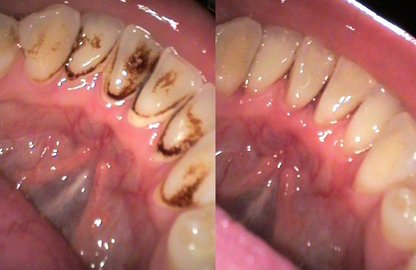

Усмішки клієнтів Pecham